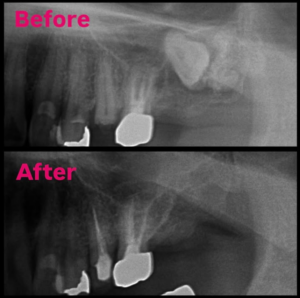

2026.01.04 親知らず抜歯 その他抜歯親知らず抜歯 智歯抜歯 歯牙種の摘出親知らずの抜歯(智歯抜歯)及び歯牙種の摘出術を行いました。経過良好です。 #松本市歯科医院#松本市歯医者#松本市#歯科#歯医者#歯科医院 #根管治療#歯の矯正#精密根管治療#マイクロスコープ#ラバーダム#インプラント#矯正#マウスピース#小児歯科#親知らず#小児矯正#プレオルソ#セラミック#ジルコニア#顎関節#嚥下